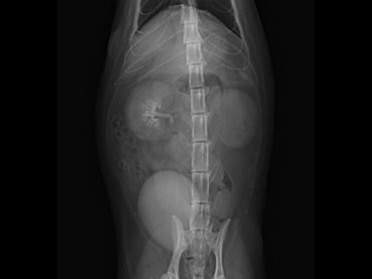

他院より紹介されたケース、この猫ちゃんは左右尿管に 結石(矢印)が詰まっていました。

尿管結石が原因で腎臓は水腎症になっていました。

左右の尿管結石が同時に詰まってしまい左の尿管が破裂(矢印)していました。

尿管結石2箇所以上閉塞による水腎症。